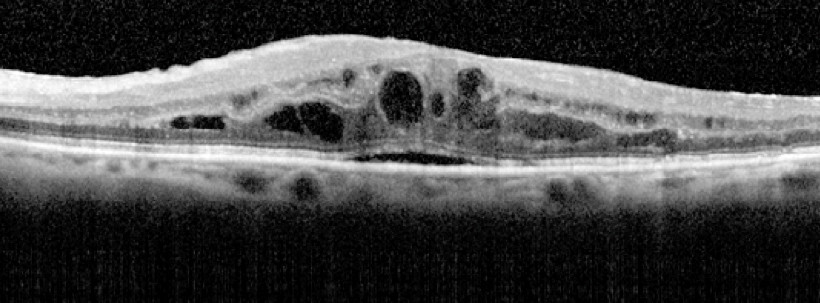

Die klinische Einführung der optischen Kohärenztomographie (OCT) hat die diagnostischen Möglichkeiten erheblich erweitert. Seit etwa 10 Jahren steht damit ein Verfahren zur Verfügung, welches hochauflösende Schnittbilder von okulären Strukturen liefert. Besonders in der Netzhaut-Diagnostik und bei der Beurteilung von Glaukomschäden hat sich das Verfahren sehr bewährt. Das Spektral-Domain-OCT (SD-OCT) mit einer axialen Auflösung von unter 5 Mikrometer liefert Bilder, die vom Detailreichtum an histologische Schnitte erinnern (Abb. 1).

Die Untersuchung ist patienten- und anwenderfreundlich und inzwischen fester Bestandteil der augenärztlichen Diagnostik. Besonders bei der Darstellung der zentralen Netzhaut im Rahmen der AMD-Diagnostik und bei verschiedenen Formen des Makulaödems ist die Methode heute unverzichtbar.